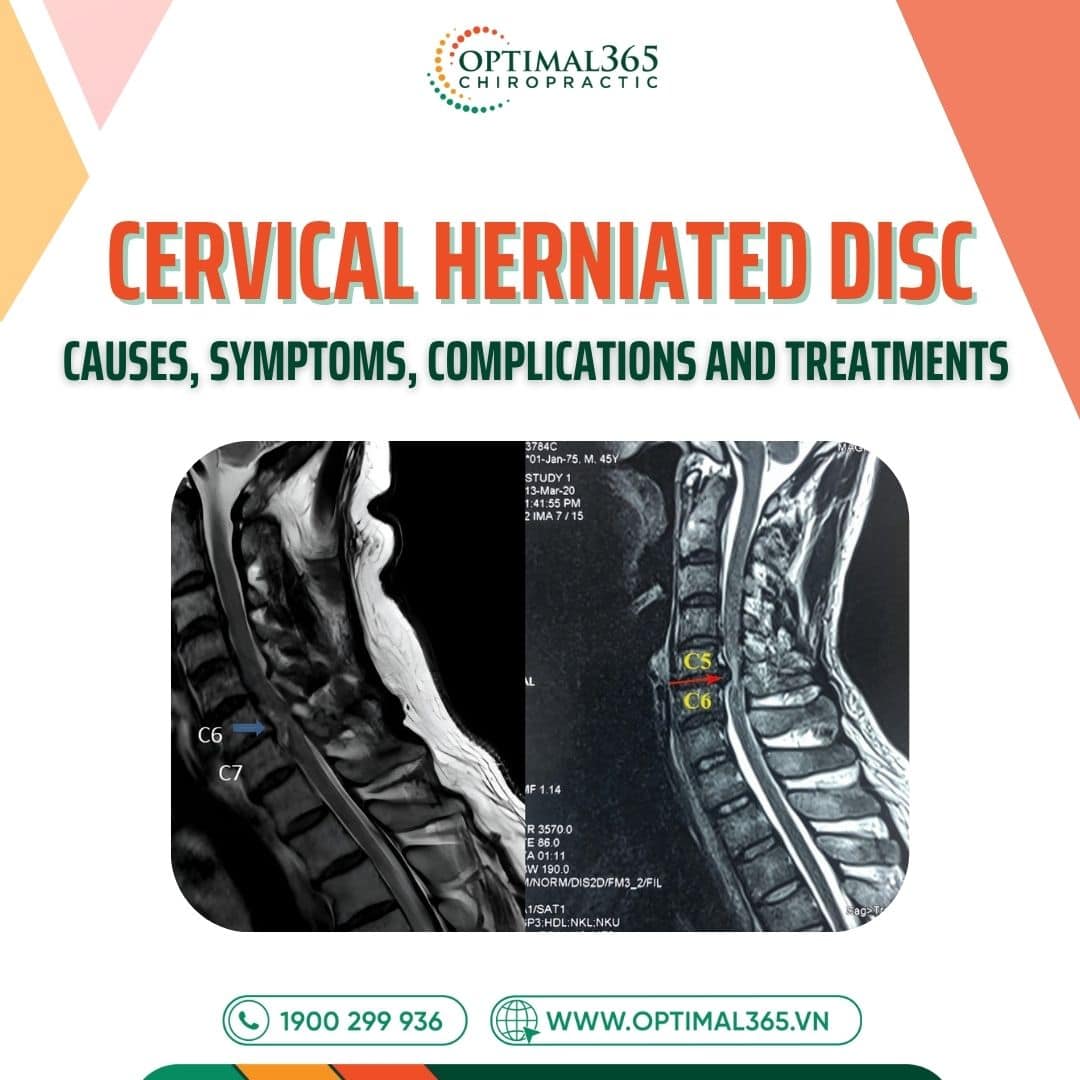

The cervical spine consists of 7 vertebrae: C1, C2, C3, C4, C5, C6, C7, connected by intervertebral discs, slightly curved in a C-shape. Each disc acts like a “rubber cushion” with a jelly-like nucleus pulposus in the center and a fibrous annulus outside, absorbing shocks and enabling spinal flexibility.

Inside the disc, the nucleus pulposus (gel-like structure) contains proteoglycans, surrounded by a circular fibrous annulus mainly made of collagen fibers. Finally, endplates between the cartilage and vertebral body protect the surface, preventing the nucleus from being compressed inward.

Cervical herniated disc happens when the disc ages, tears, or suffers trauma. At this point, the nucleus pulposus protrudes from the annulus, compressing nerve roots or the spinal cord, causing pain and various symptoms.

Cases with multiple discs herniating simultaneously lead to multi-level cervical herniated disc, with higher complication risks. Here, pressure on the spine is much greater than in single-level herniation.

In subclinical cases, cervical herniated disc symptoms are detected via MRI showing: Disc herniating anteriorly or posteriorly, nucleus pulposus displaced, spinal structure changes, and compression on nerve roots or spinal cord.